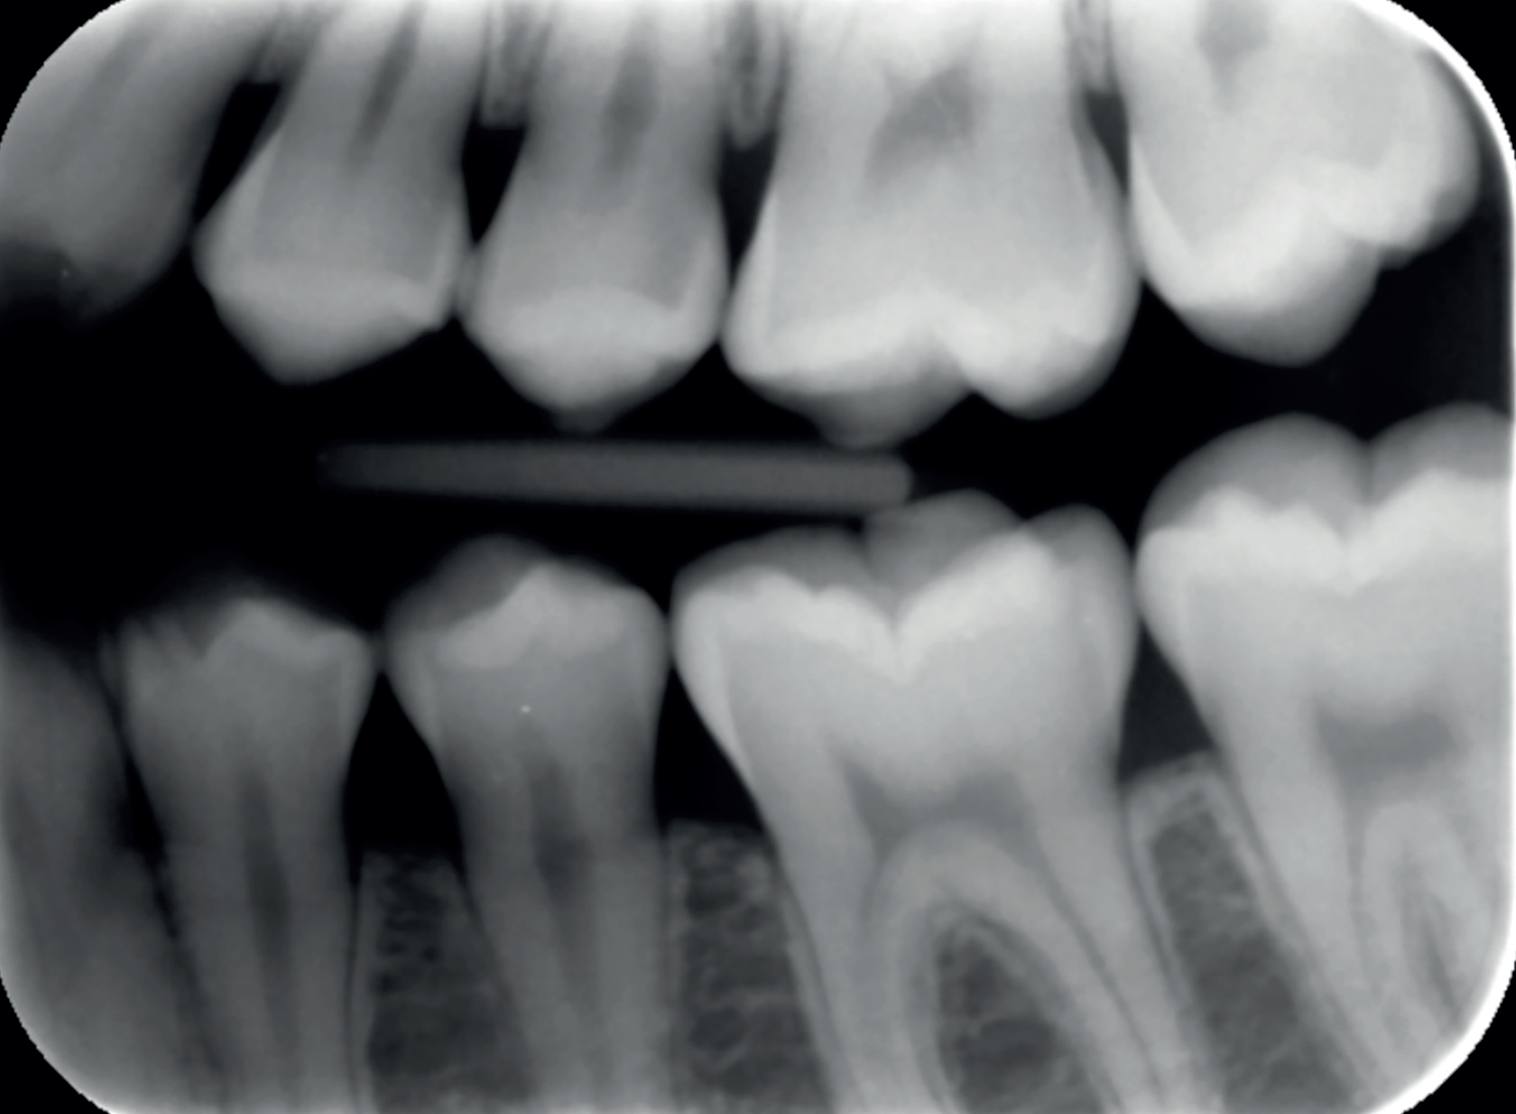

A 17-year-old female patient presented for a routine six-month examination without complaints or concerns regarding her teeth. I noted a small colour change on the upper left premolar during the examination with five times magnification loupes.

An X-ray confirmed the presence of a cavity, which was highlighted using a second-opinion AI software (Figures 1 and 2). Given the cavity’s location in the visible smile line and the patient’s age, I opted for a tooth-coloured filling rather than the NHS amalgam option. I chose Stela, a high-performance selfcure composite, for its aesthetic and functional qualities.

Figure 1: Routine bitewing